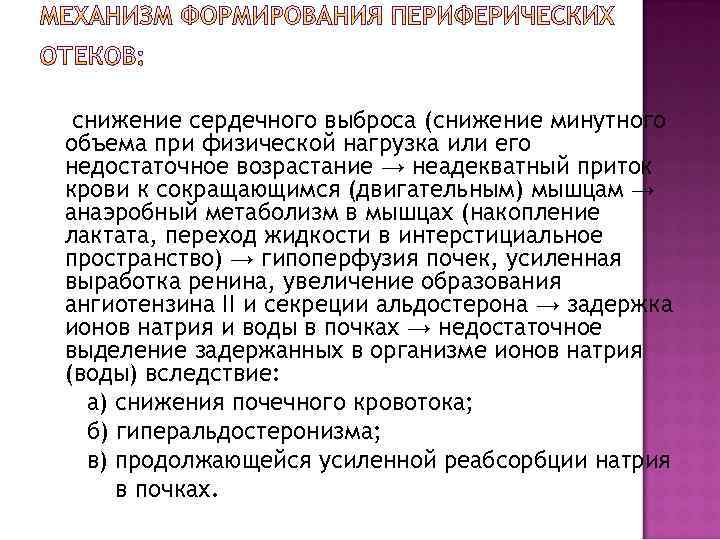

снижение сердечного выброса (снижение минутного объема при физической нагрузка или его недостаточное возрастание → неадекватный приток крови к сокращающимся (двигательным) мышцам → анаэробный метаболизм в мышцах (накопление лактата, переход жидкости в интерстициальное пространство) → гипоперфузия почек, усиленная выработка ренина, увеличение образования ангиотензина II и секреции альдостерона → задержка ионов натрия и воды в почках → недостаточное выделение задержанных в организме ионов натрия (воды) вследствие: а) снижения почечного кровотока; б) гиперальдостеронизма; в) продолжающейся усиленной реабсорбции натрия в почках.

снижение сердечного выброса (снижение минутного объема при физической нагрузка или его недостаточное возрастание → неадекватный приток крови к сокращающимся (двигательным) мышцам → анаэробный метаболизм в мышцах (накопление лактата, переход жидкости в интерстициальное пространство) → гипоперфузия почек, усиленная выработка ренина, увеличение образования ангиотензина II и секреции альдостерона → задержка ионов натрия и воды в почках → недостаточное выделение задержанных в организме ионов натрия (воды) вследствие: а) снижения почечного кровотока; б) гиперальдостеронизма; в) продолжающейся усиленной реабсорбции натрия в почках.